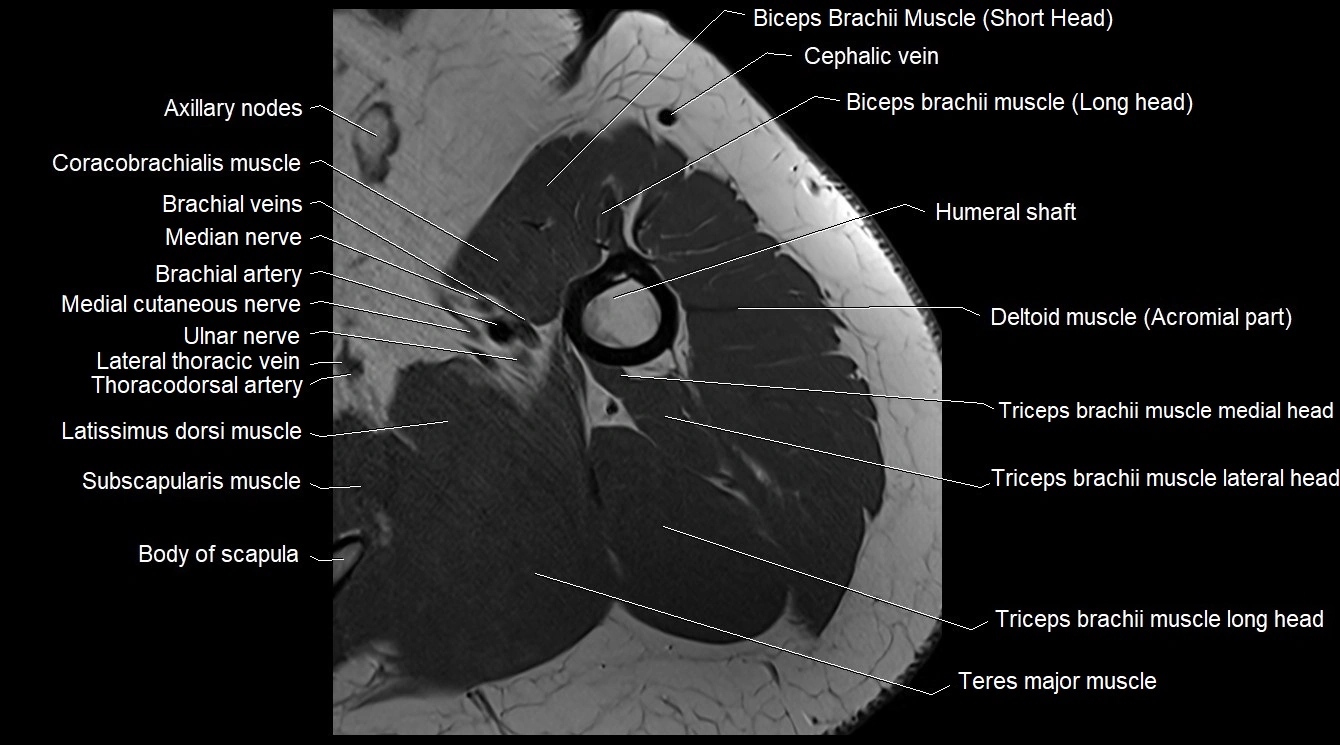

- Axillary lymph nodes

- Coracobrachialis muscle

- Brachial artery

- Median nerve

- Subscapularis muscle

- Body of scapula

- Teres major muscle

- Triceps brachii muscle

- Long head of triceps brachii muscle

- Lateral head of triceps brachii muscle

- Medial head of triceps brachii muscle